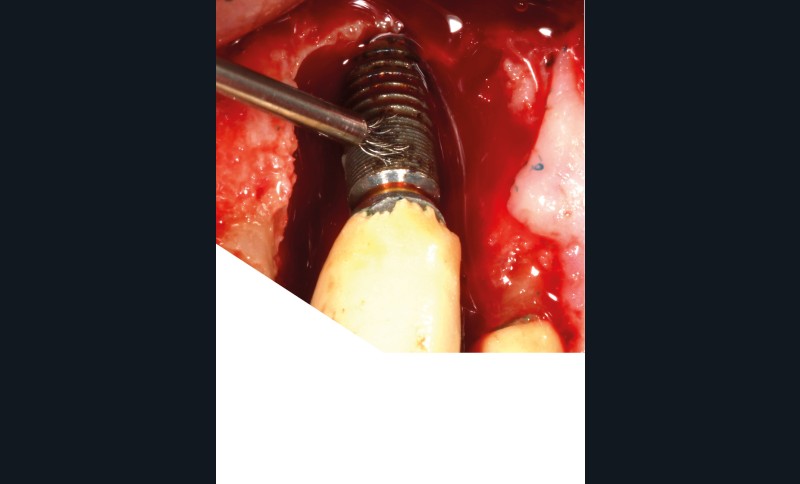

L’implant

- Site 23

- Mis en place il y a 12 ans

- Parmi ces longueurs d’onde, deux lasers (Er-YAG et Diode) sont intéressants dans le traitement de la péri-implantite :

– Le laser Er-YAG, utilisé pour le nettoyage, est un laser avec un milieu actif composé d’yttrium, d’aluminium et de grenat dopé à l’erbium. Avec une longueur d’onde de 2 940 nm situé dans l’infrarouge, le laser Er-YAG est un laser à haute énergie, dont la lumière est absorbée dans l’eau et dans l’hydroxyapatite et qui ne pénètre pas profondément. Ceci permet de couper des tissus mous et des tissus durs, mais également de désorganiser le biofilm bactérie.